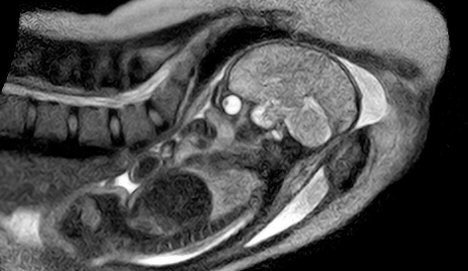

Baby's brain scan during birth

A team comprised of obstetricians, radiologists and engineers have built an "open" MRI scanner that allows a mother-to-be to fit fully into the machine and give birth there, the hospital announced on Tuesday.

The MRI (magnetic resonance imaging) scanner has already taken unique images of the body of a mother and the movement of her baby through the birth canal to the point where its head emerges into the world. The birth that took place in the scanner went smoothly and both mother and baby were in good health, a hospital spokeswoman said.